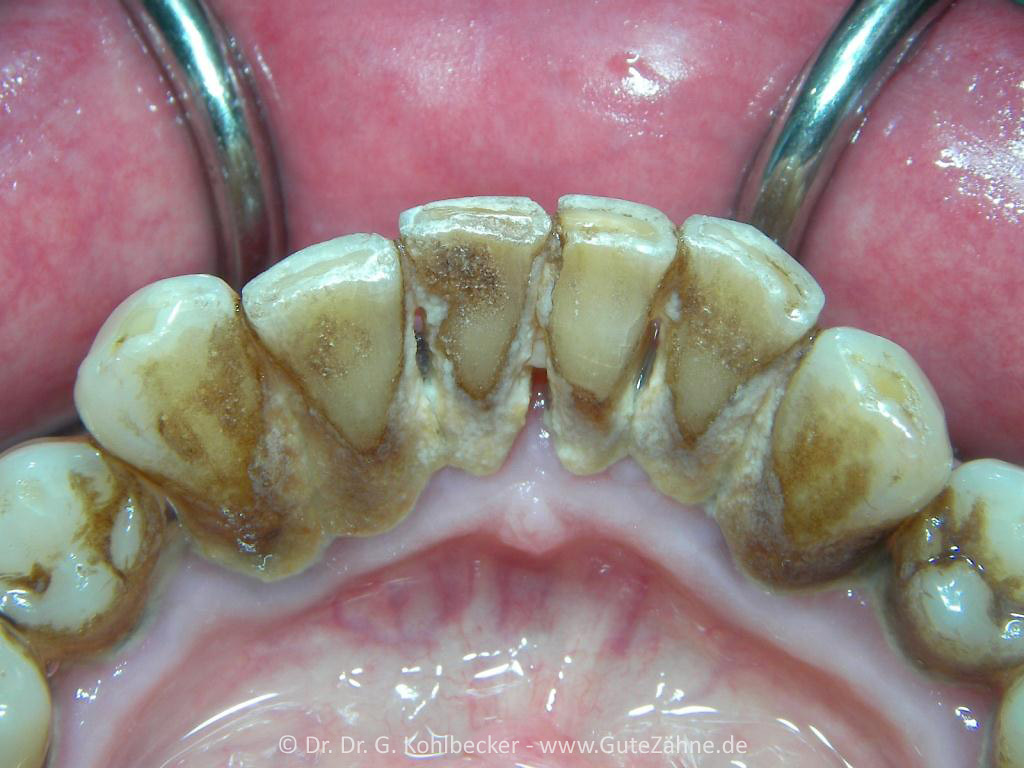

Zahnstein so weit das Auge reicht